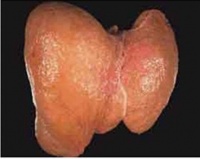

脂肪肝是一种多病因引起的脂肪大肝细胞内异常积累的病理状态。这种病理状态是肝脏对各种损伤产生的最常见反应。